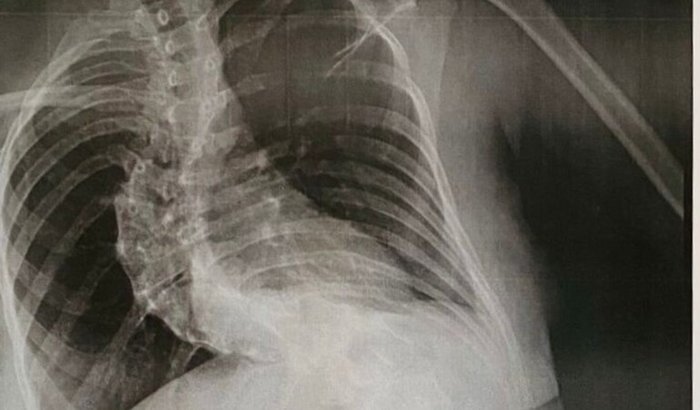

Olá, eu sou a Rafaeli Borin e estou aqui para compartilhar a história da minha querida amiga, Tamily Ester. Natural de Artur Nogueira (SP), Tamily vive com escoliose há anos e, apesar de sua força e determinação, a curvatura na coluna vem causando dores intensas e limitando suas atividades diárias.

Agora, chegou o momento de realizar a cirurgia corretiva que pode devolver à Tamily a qualidade de vida e o bem-estar que ela tanto merece. Esse procedimento de alta complexidade tem um custo elevado, envolvendo equipe médica especializada, internação hospitalar e materiais específicos. Por isso, precisamos do apoio de quem puder contribuir.